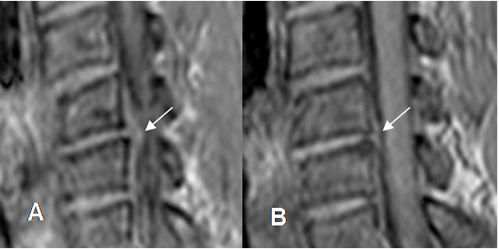

Fig 109. Regresión de hernia.

A y B: RM axial en T2. Hernia paramediana derecha. En un control posterior, ha disminuido el tamaño y la compresión de las raíces.

Fig 110. Regresión de hernia.

A y B: RM sagital en T2. Hernia mediana en L3-L4, que después de 7 meses, muestra disminución de su tamaño y menor compresión del saco dural. Cambios degenerativos en las placas terminales de L3-L4 y

L4-L5 y artefactos sobre el cuerpo de L4, ocasionados por materia de fijación posterior. (Puntas de flecha).